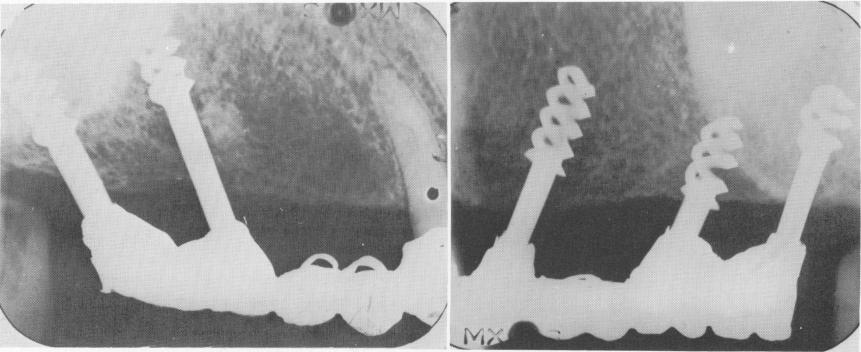

Fig. 4-18. Chercheve's spiral-post implants in both the mandible and maxillae.

1 Chercheve`s spiral-post endosseous implants in mandible and maxillae